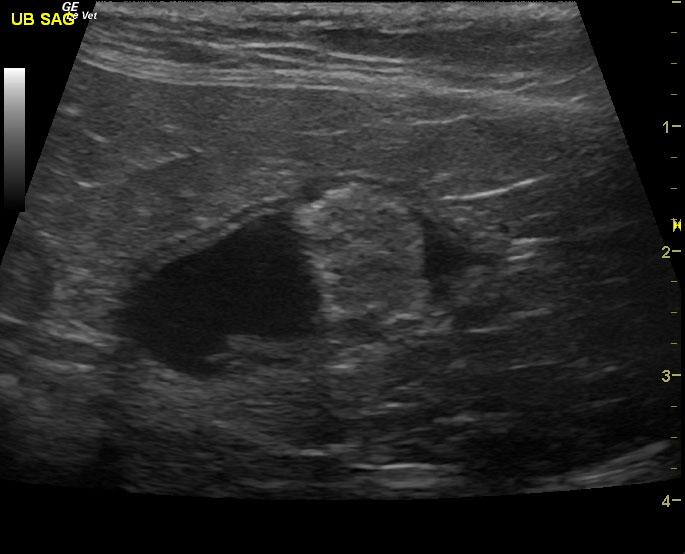

A 16-year-old neutered male DSH cat with a history of weight loss and inflammatory bowel disease was presented for poor appetite. Dehydration, dental disease, and nasal discharge were noted on physical examination. Hematuria was present on urinalysis. Initial CBC showed leukocytosis and anemia, which remained fairly unchanged after a month of antibiotic therapy.